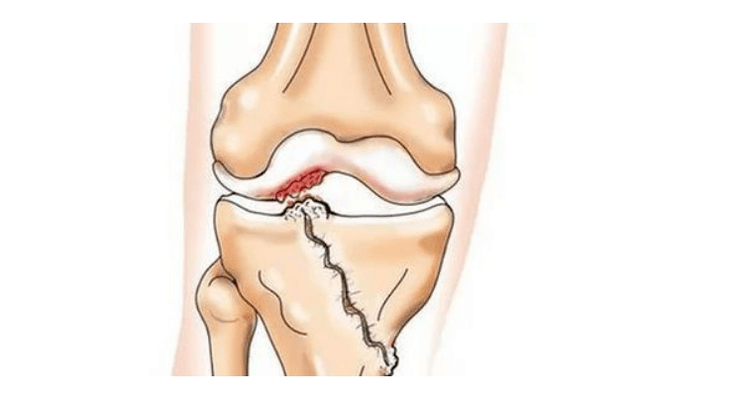

- injuries (fractures, meniscal and anterior cruciate ligament ruptures).Unfortunately, in any person, regardless of age, these injuries lead to excessive stress on the cartilage.A fracture of any part of the bones covered with cartilage is accompanied by the formation of an unevenness - a “step”.In this area, when moving, abrasion occurs and arthrosis forms;

With arthrosis (osteoarthrosis), in addition to the progressive destruction of cartilage, loss of its elasticity and shock-absorbing properties, bones are gradually involved in the process.Under load, sharp edges (exostoses) appear, which are mistakenly considered “salt deposits” - with classic arthrosis, no salt deposition occurs.As arthrosis progresses, it continues to “eat” the cartilage.Then the bone becomes deformed, cysts form there, all structures of the joint are affected, and the leg becomes bent.

Lack of cartilage in most affected areas, severe sclerosis (hardening) of the bone, many osteophytes and a sharp narrowing or absence of the joint space.The pain is almost constant, gait is impaired.Mobility is sharply limited, and joint deformation is noticeable.NSAIDs, physiotherapy and other standard methods of treating knee arthrosis are ineffective.